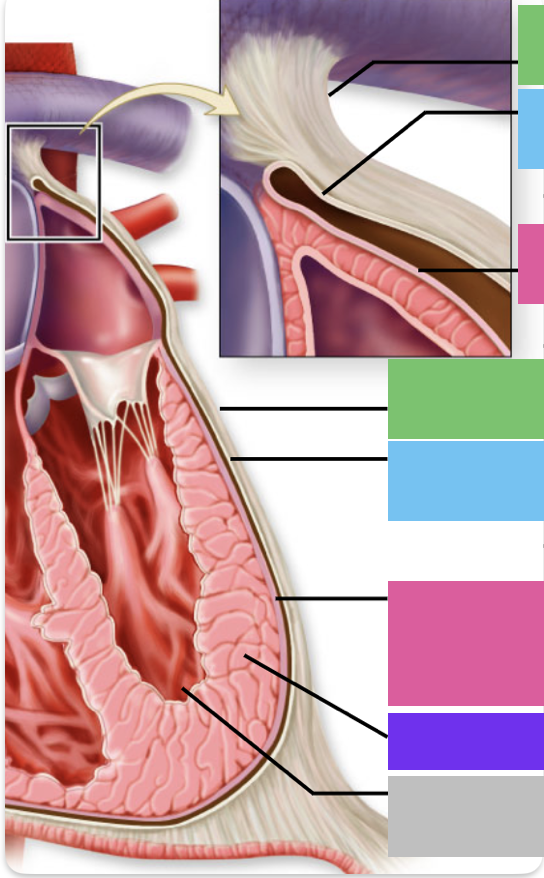

fibrous pericardium

blue

parietal pericardium

pink

visceral pericardium (connective tissue) / epicardium (muscle)

purple

myocardium

grey

endocardium

blue

trabeculae carneae - only in ventricles

orange

papillary m.

chordae tendineae